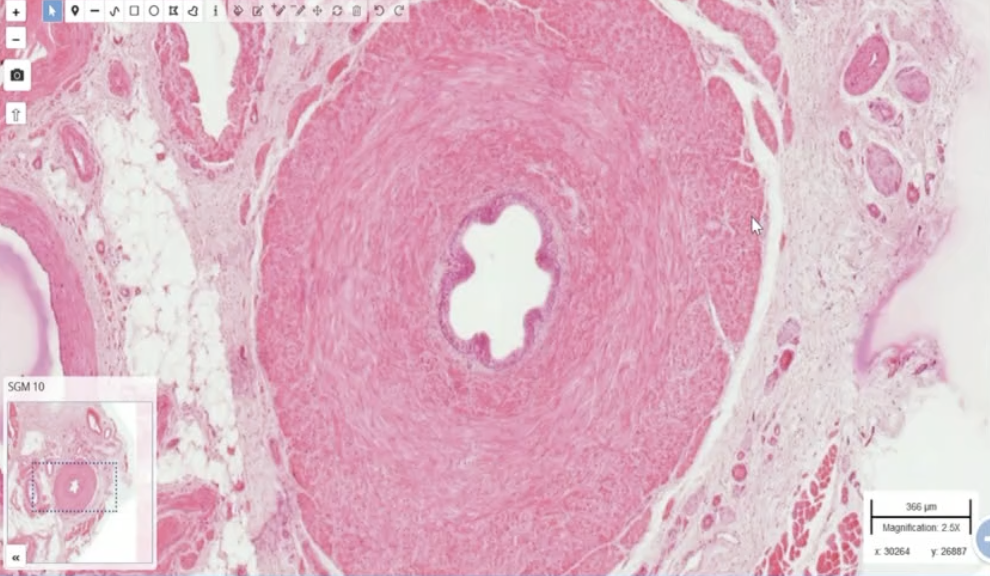

Q

Quel vx?

A

Artère (certes, biscornue)

=> On voit bien la limite de la média et de l’adventice

=> Épaisseur régulière, compacte, homogène sur tout le porutour